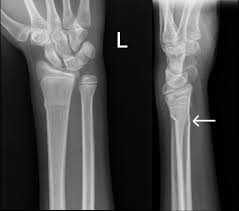

How Do Doctors Treat A Buckle Fracture With Pictures

How Do Doctors Treat A Buckle Fracture With Pictures from images.wisegeek.com